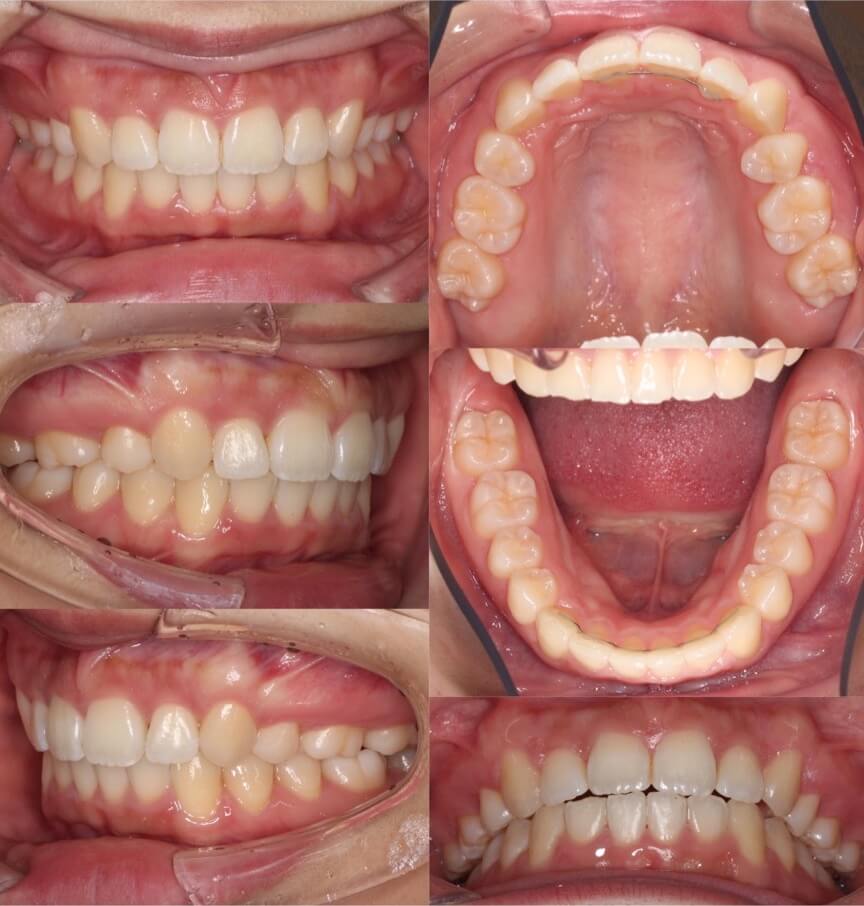

20代女性・唇側矯正装置・2本抜歯

過蓋咬合の治療方法で、上下どちらの前歯を圧下させるか、歯並びや歯の見え方で選択します。この症例は、上の前歯が下に落ちていると言うより、下の前歯が上に突き上げているタイプであったため、下の前歯を圧下させました。

<症例概要>

主訴:前歯の突出

年齢・性別:高校生女性

住まい:千葉県八千代市

症状:過蓋咬合・上顎前突

治療方針:下顎前歯の圧下・抜歯空隙の閉鎖

抜歯:上左右4番(計2本)

治療期間:2年6か月

リテーナー:上下フィックスタイプ+上下プレートタイプ

治療費用:968,000(税込)

代表的副作用:痛み・治療後の後戻り・歯根吸収・歯髄壊死・歯肉退縮

▶︎その他の副作用